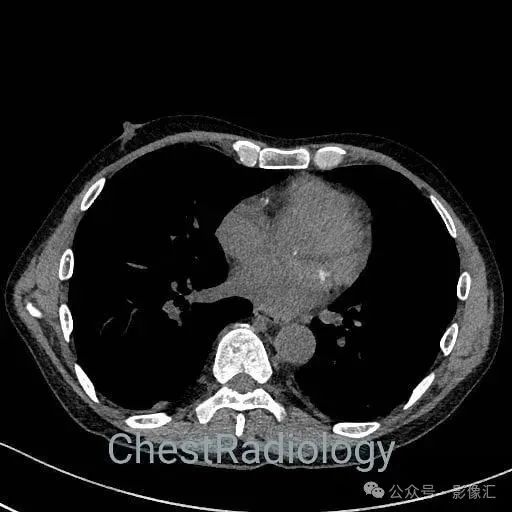

咯血患者,肺部弥漫磨玻璃,细节决定成败?

成年男性,咯血,细节决定成败,你看到了吗?欢迎评论区留言